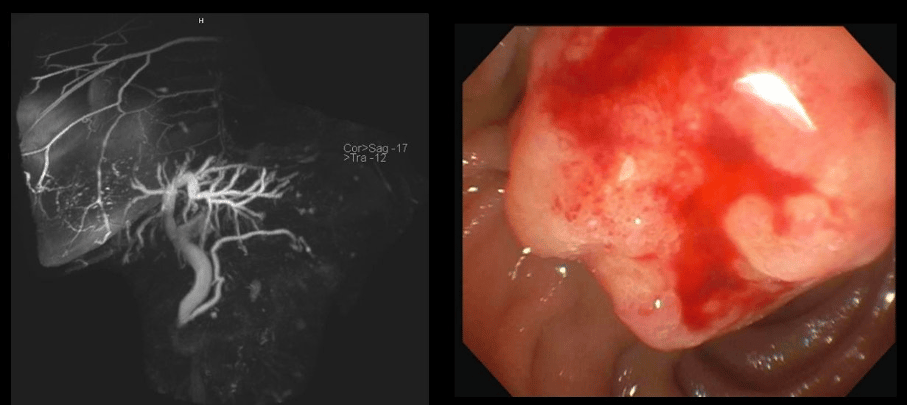

A female patient in her late 70’s with status post cholecystectomy and a history of breast cancer on anastrozole, which was stopped 1 month prior because of itching was found to have elevated liver tests (alkaline phosphatase up x 4, ALT up x 6, AST up x 4). MRCP showed dilated common bile duct to 11 mm with smooth tapering at ampulla of Vater. The patient was sent for EGD and endoscopic ultrasound (EUS). The liver tests had decreased by 50% on the day of the procedure. The ampulla had the above appearance on EGD with a distal cap. What would you do next?

We opted for an ERCP first, given the higher risk of EUS-FNB induced pancreatitis without a protecting prosthesis and lower perceived risk of intraductal and ampullary sampling following sphincterotomy to separate the PD and CBD orifices.

The selective cannulation was aided by waiting for a hint of bile to aim for the CBD opening given that landmarks were not clear with the ulcerated surface of the ampulla.

The issue with pure EUS core sampling and mucosal biopsies is risk of ampullary hematoma, biliary obstruction and pancreatitis.

Further, with the appearance noted in this case, and relatively small lesion, yield of core biopsies with 22G needle will be limited, and pancreatitis with 19G sampling is a high risk (many experts would quote same risk of pancreatitis as ampullectomy when large caliber FNB is used in this location). Lastly, with highly suspicious endoscopic appearance of the lesion, a negative round of sampling is not sufficient to stop the evaluation. Hence, biliary prosthesis placement is a reasonable approach. As we see in this case, sampling was not conclusive and best next step is to repeat biopsies vs proceeding with ampullectomy as a diagnostic and therapeutic technique with PD stent placement (imperative) given age and comorbidities, I favor the former. If this is negative then shared decision making with the patient and ampullectomy would be the next step in my opinion.